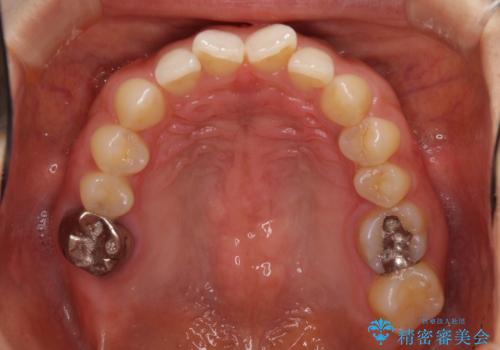

- 前歯の隙間と奥歯の目立つ銀歯を気にして来院された患者様です。

インビザラインにより下顎前歯の隙間を閉じるとともに、奥歯の咬み合わせを改善させることとしました。

矯正治療後には、銀歯のクラウンをセラミッククラウンへ替える補綴治療を行うこととしました。

左右奥歯の咬み合わせを変更させる必要があったため、治療期間は長くなることが予想されました。